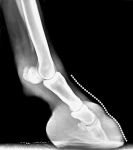

rtg1Na RTG snímcích (větší obrázky naleznete v galerii pod článkem) je zachycena pravá přední končetina klisny Denali, pořízená technikou nepřímé digitalizace. Bohužel tyto snímky nejsou pořízené standardně, nejen co se týče úpravy kopytního pouzdra, ale i ohniskové vzdálenosti rentgenovaného objektu. Rentgeny byly provedeny 8. 4. 2011 a 21. 1. 2012. Mezi tím tedy uběhlo 3/4 roku.

Na chronologicky prvním snímku, tj. 8. 4., byl úhel kopytní kosti o 1-2° strmější než na druhém po skoro devíti měsících léčby. Stupeň rotace odhaduji na podobný, ale těžko posouditelný, protože bylo upravované kopytní pouzdro. Tedy na prvním snímku (s řetízkem) je sklon kopytní kosti 52° a úhel stěny se po orašplování snaží kopírovat kopytní kost. Je tam jasná výplň vmezeřenou tkání. Z toho usuzuji, že schvácení je už na prvním obrázku staršího data. Díky orašplování to skoro vypadá, že tam v podstatě není rotace…